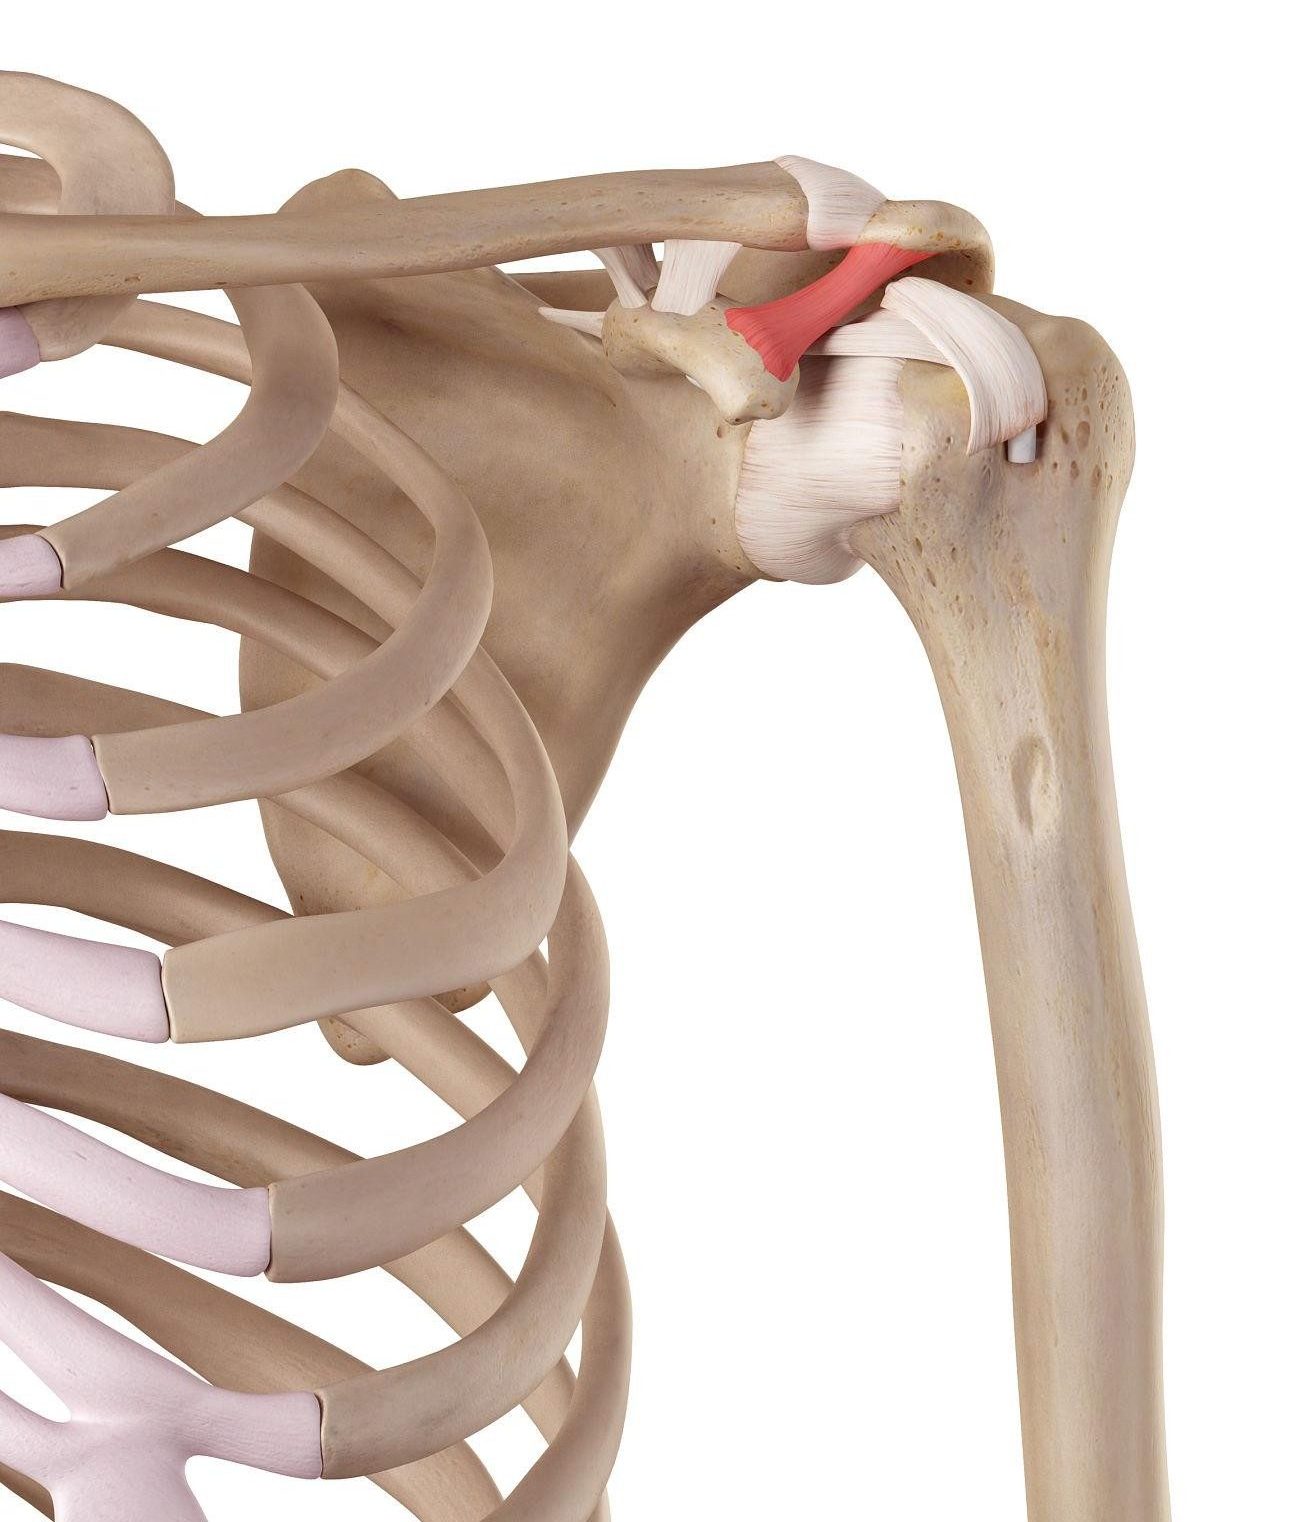

A shoulder separation is often confused with a shoulder dislocation. However, it does not involve the main ball-and-socket joint. Instead, it affects the acromioclavicular (AC) joint — the joint where the collarbone (clavicle) meets the acromion of the shoulder blade.

Understanding the AC Joint

The AC joint is stabilized by two main ligament groups:

- AC ligaments – surround the joint itself

- Coracoclavicular (CC) ligaments – connect the clavicle to the shoulder blade underneath

These ligaments keep the collarbone aligned with the shoulder blade during arm movement.